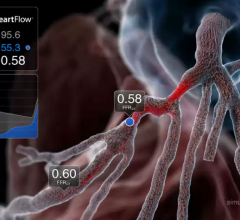

September 11, 2012 — Data presented at the 2012 ESC Congress in Munich from the prospective DeFACTO study show that, when compared to standard coronary angiography, the noninvasive assessment of fractional flow reserve by computed tomography (FFR-CT) provides a more accurate determination of which lesions require invasive evaluation.